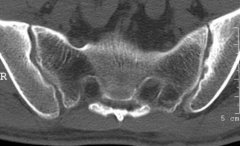

QZ16030094 姓名:陈先生 性别:男 年龄:32岁

- 病情

AS ①晚期 ②重度 病史:5年+

- 治疗

治疗后骶髂关节疼痛消失,腰椎前屈、背伸侧弯活动自如,膝关节无压痛感,复查血沉、C反应蛋白、等各项检查均已达到临床康复的标准。